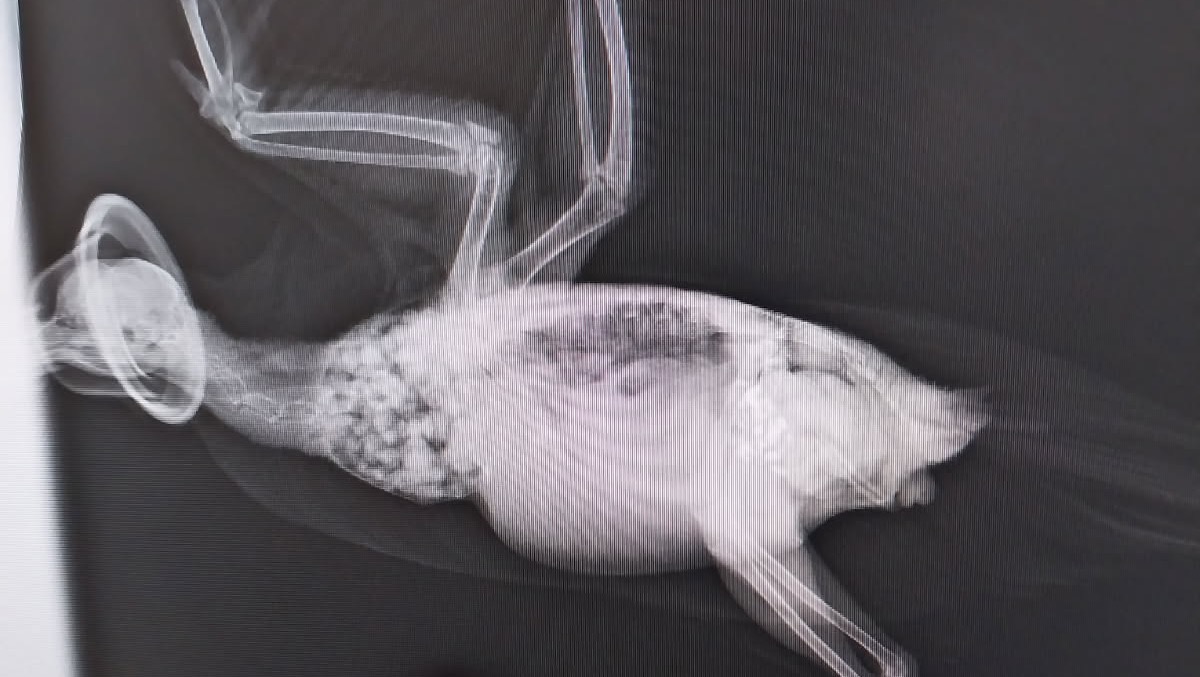

Three days ago, I met Margaret, a gentle pigeon whose story truly broke my heart. She had been trapped for several days inside a residential building with no food or water. When I found her, one of her wings was drooping — she could only walk but couldn’t fly. The wing felt swollen and possibly fractured, and her big beak and calm eyes told me she was an older bird who had already been through a lot.

On the first day after her rescue, Margaret was terrified — she wouldn’t eat or drink, and just sat quietly in the corner. I knew she needed urgent help, so I took her to Dr. Nat at Campsie Vet. After an X-ray under anesthesia, we discovered her elbow was broken, most likely from a strong collision.